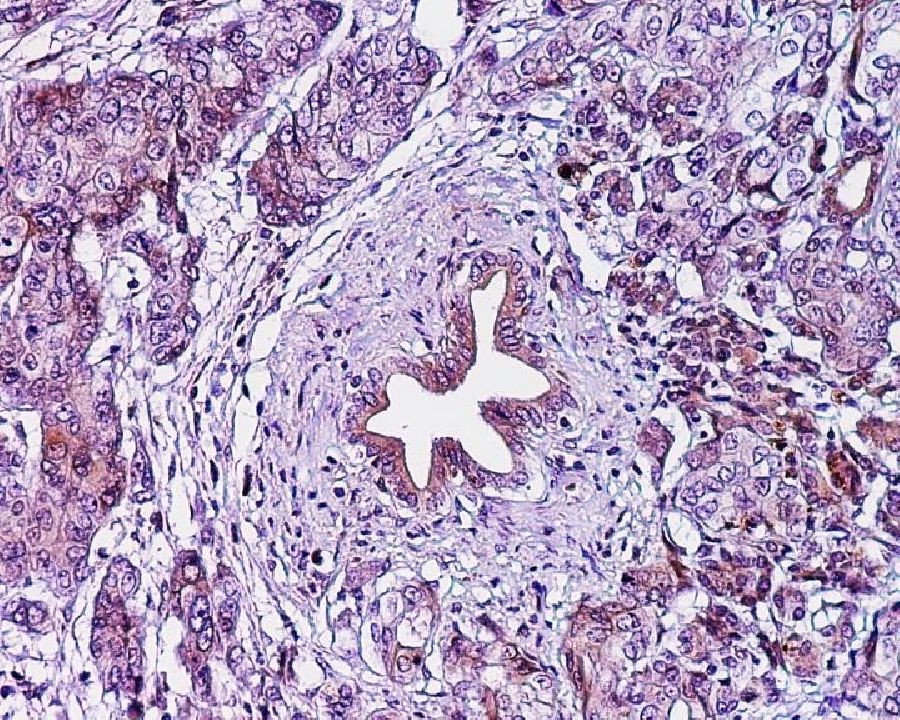

Expertos reclaman la inversión necesaria para reducir las tasas de mortalidad por cáncer de páncreas en Europa

Los investigadores han hecho un llamamiento a los responsables políticos europeos para que destinen los recursos adecuados a la lucha contra el cáncer de páncreas, una enfermedad casi siempre mortal en la que apenas se ha avanzado en los últimos 40 años. Las últimas predicciones sobre las muertes por cáncer en la UE y el Reino Unido para 2021, publicadas en la revista `Annals of Oncology`, muestran que las tasas de mortalidad por cáncer de páncreas se mantendrán aproximadamente estables en los hombres, pero seguirán aumentando en las mujeres de la mayoría de los países de la UE.

El profesor La Vecchia explica que "entre los principales cánceres, el de páncreas es el cuarto más común y sigue siendo el único que no muestra una caída general en las tasas de mortalidad en las últimas tres décadas en Europa en ambos sexos. Es importante que los gobiernos y los responsables políticos proporcionen recursos para la prevención, el diagnóstico precoz y el tratamiento del cáncer de páncreas con el fin de mejorar estas tendencias en un futuro próximo", reclama.

"Si el cáncer se detecta temprano, es más fácil de tratar con éxito, pero la mayoría de los casos están avanzados en el momento del diagnóstico --prosigue--. Evitar el tabaquismo y el consumo excesivo de alcohol, controlar el peso y, por ende, la diabetes son las principales formas que conocemos para ayudar a prevenir la enfermedad, pero solo representan una proporción de los casos. Los medicamentos nuevos y dirigidos están produciendo alguna mejora en el tratamiento, pero es difícil cuantificar su impacto potencial en la actualidad".

El investigador destaca que los resultado de este nuevo informe "son particularmente importantes porque enfatizan el hecho de que las tendencias en la mortalidad por cáncer de páncreas y cáncer de pulmón femenino no muestran el patrón positivo de otros cánceres importantes, lo que subyace a la necesidad de mayores esfuerzos para la investigación y el control de estas neoplasias".